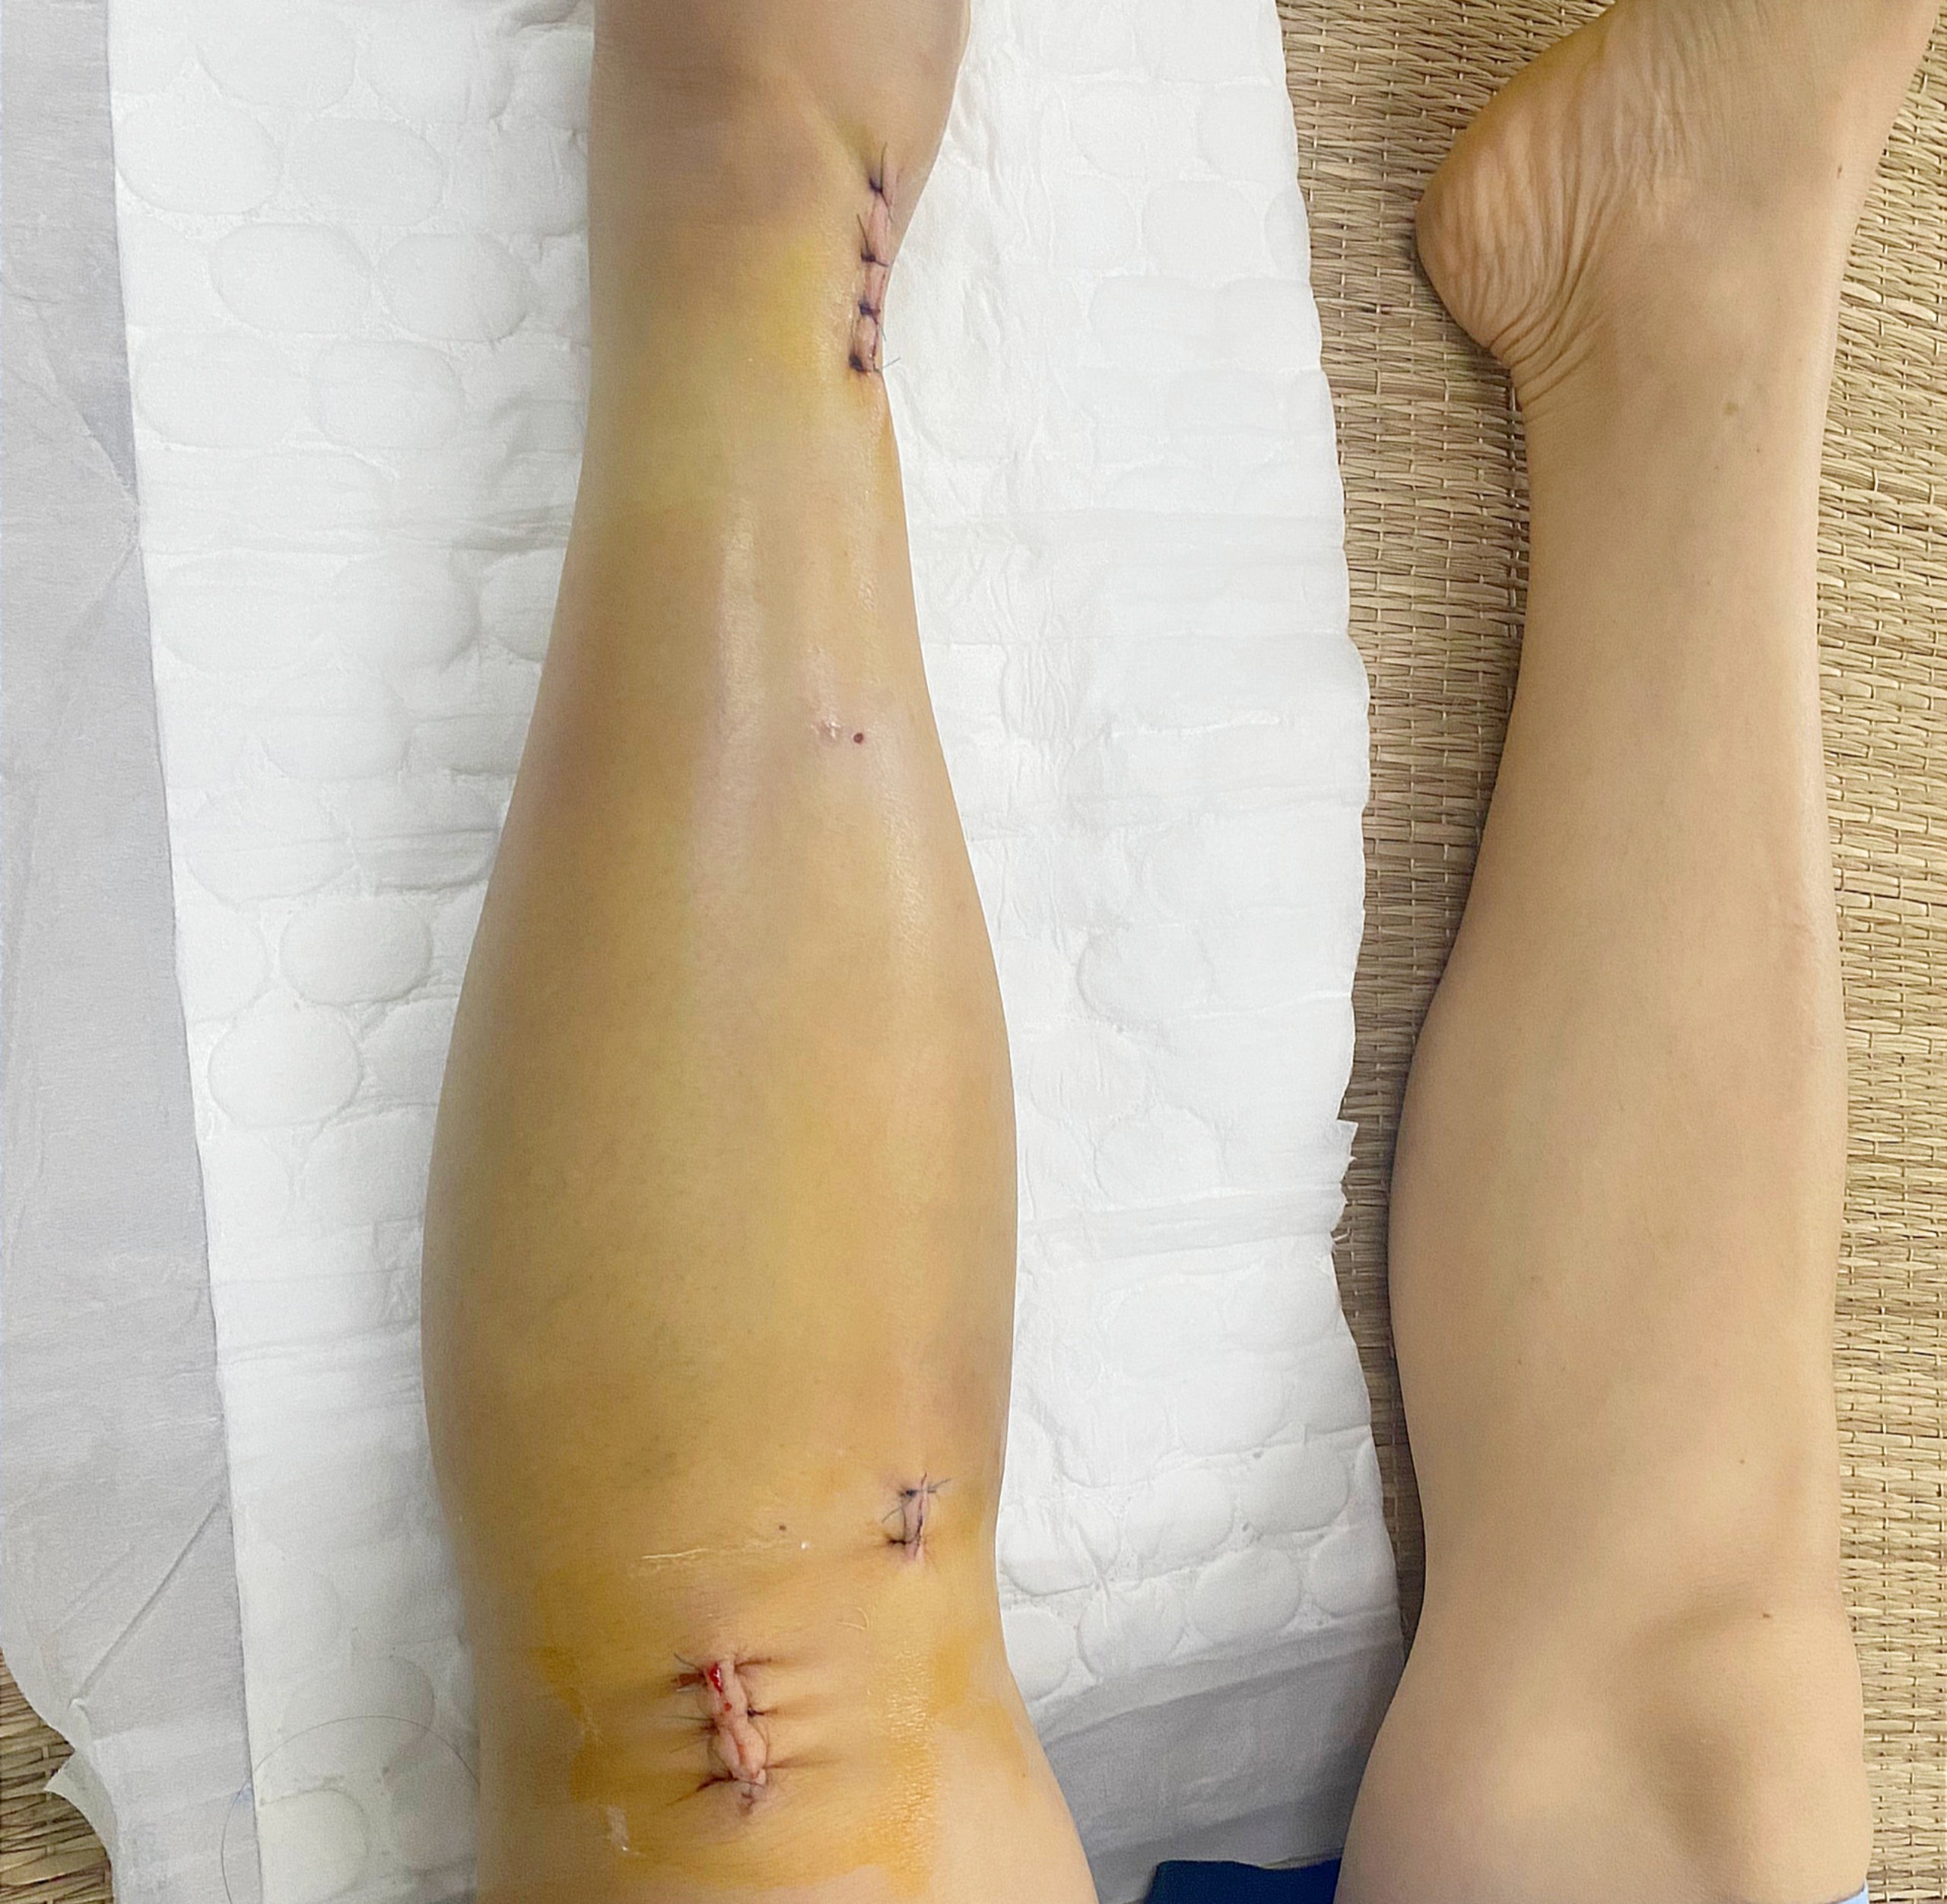

Chân trái của bệnh nhân T. sau khi phẫu thuật kết hợp xương bằng nẹp vít sử dụng hệ thống C-arm

Sau 1 giờ phẫu thuật dưới hướng dẫn của hệ thống C-arm, kết quả kiểm tra phim chụp X-quang 2 xương cẳng chân của bệnh nhân cho thấy xương nắn chỉnh tốt. Sau mổ 1 ngày bệnh nhân đã giảm đau rõ rệt và đã có thể tập vận động. Sau phẫu thuật 7 ngày, tình hình sức khỏe của bệnh nhân hồi phục tốt và đã được ra viện vào ngày 02/10/2023.

BSCKI. Đào Văn Quang, Phó Trưởng khoa Chỉnh hình – Bỏng Bệnh viện Đa khoa tỉnh Thanh Hóa cho biết: “Đối với những trường hợp chấn thương như bệnh nhân T., việc sử dụng phương pháp phẫu thuật kết hợp xương bằng đinh nội tuỷ có chốt đóng kín dưới hướng dẫn của hệ thống C-arm là phương pháp tối ưu nhất. So với phương pháp mổ mở thông thường thì phương pháp nắn kín kết hợp xương trên C-arm này có nhiều ưu điểm hơn như: Hệ thống C-arm giúp cho các phẫu thuật viên định hướng đặt các đinh ốc vít vào xương được chính xác hơn và không cần phải mổ rộng chỗ cần can thiệp ra, hạn chế nhiễm trùng vì vẫn giữ được ổ gãy kín, hoặc chỉ mở tối thiểu. Bảo toàn được cấu trúc giải phẫu, nhất là mạch máu thần kinh và gân cơ, đảm bảo được hoàn hảo về chức năng chi thể và tính thẩm mỹ. Bệnh nhân ít đau đớn hơn. Chi phí điều trị thấp hơn, bởi thời gian nằm viện chăm sóc ngắn hơn, thuốc dùng ít hơn…”.